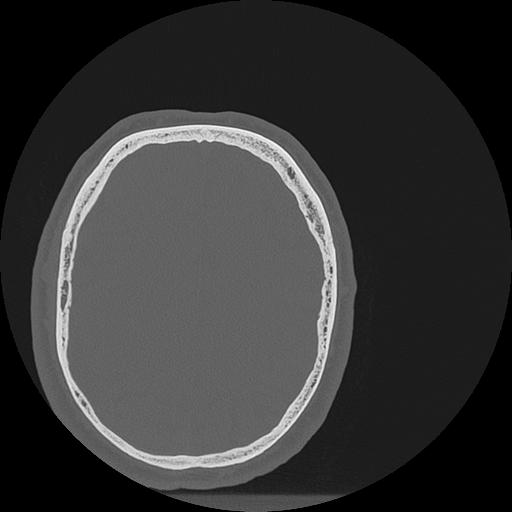

7 HUESO,,Vol,0.5,HUESO,,